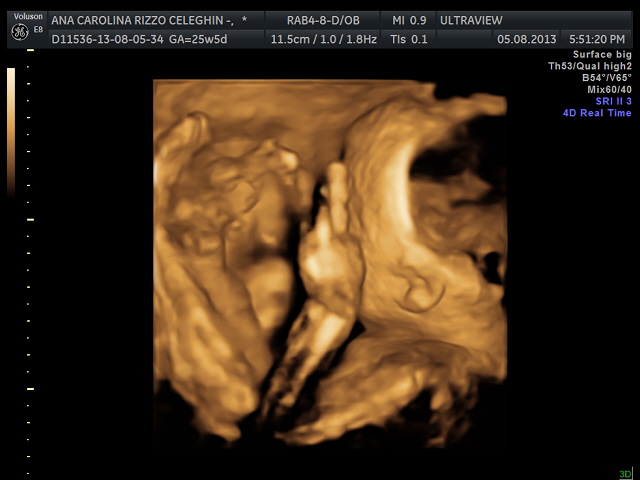

Entre as semanas 26 e 27, eu fiz o ultrassom 3D,

acho que nunca havia ficado tão emocionada em toda minha vida (com exceção do

dia de meu casamento... claro... eu acho... hehehe). O Lucas estava todo torto,

com as duas perninhas na cabeça e o rostinho virado, foi necessária uma hora de

sessão de ultrassonografia, duas barras de chocolate, várias balinhas, alguns

copos de água gelada e muitos cutucões até conseguirmos obter boas fotos.

| Carolina e Ricardo Productions orgulhosamente apresentam: Lucas |